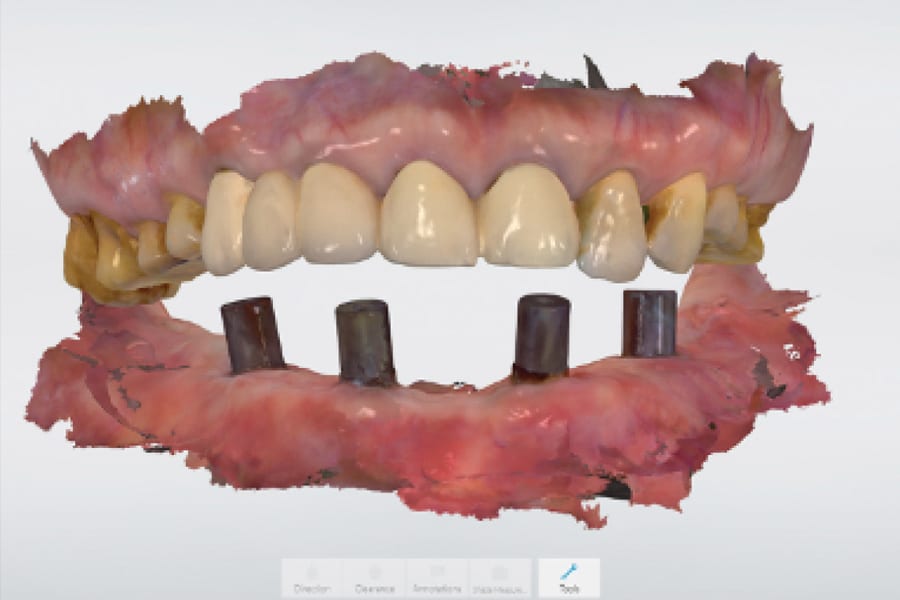

Delivery of the Definitive Prosthesis

After osseointegration and soft-tissue healing the interim prosthesis was removed intraorally revealing healthy soft tissue without evidence of inflammation (Figure 20). Scan bodies were placed on the implants and intraoral scanning (TRIOS 3) was performed to record both the positions of the scan bodies and the soft tissue of the lower arch (Figure 21). The scan bodies were then removed intraorally and photogrammetry dominos (iCam 4D, Voxel Dental, voxeldental.com) were connected to the MUAs for the capturing of the implants' positions extraorally (Figure 22). The intraoral scanning and photogrammetry digital data were merged into the proprietary software and exported to the CAD software (exocad) to design a full-arch implant-supported fixed prosthesis (Figure 23). The design would forgo ti-bases and utilize Rosen screws (Rosen Implant Solutions, rosen-implant-solutions.com) to directly connect the prosthesis to the MUAs, increasing prosthetic thickness at those connections. The definitive prosthesis was milled from a zirconia block (BSM Aconia® SHT-ML 98x25mm, Besmile Dental America, bsmdental.com) on a milling unit (XMill 500 Plus, XTCera, en.xtcera.com).